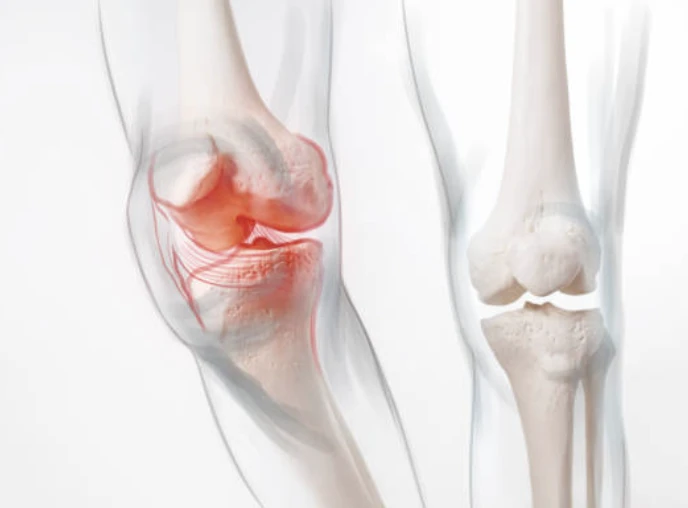

무릎의 구조

무릎이 어떤 부분으로 구성되어있는지 간략하게 살펴보겠습니다. 무릎은 들어 올리기, 무릎 꿇기 등의 일상적인 활동과 걷기 및 달리기, 에어로빅과 같은 고강도 활동으로 인해 많은 스트레스를 받는 취약한 관절입니다. 무릎 통증 원인은 이유가 다양할 수 있습니다.

각 뼈의 끝은 충격을 흡수하기 위해 연골층이 덮여있습니다. 기본적으로 무릎은 근육과 인대 그리고 힘줄에 의해 결합된 2개의 다리뼈입니다.

힘줄은 근육과 뼈를 연결하는 질긴 조직입니다. 인대는 뼈와 뼈를 연결하는 조직의 탄성 밴드와 같은 역할을 합니다. 무릎의 일부 인대는 관절의 안정성과 보호를 제공하지만, 다른 인대는 정강이 뼈의 앞뒤 움직임을 제한합니다.

무릎 통증 원인

일반적인 무릎 통증 원인은 무엇일까요?

- 염좌 또는 긴장된 무릎 인대와 근육은 일반적으로 무릎에 대한 타격이나 무릎의 갑작스러운 비틀림으로 인해 발생합니다. 해당 증상으로는 통증, 붓기, 움직이지 못함 등이 있습니다.

- 무릎 연골 손상은 무릎 외상으로 인해 반월판(충격 흡수제 역할)이 찢어지는 것입니다. 연골 파열은 종종 염좌와 함께 발생할 수 있는데, 치료방법에는 추가 부상으로 부터 무릎을 보호해 줄 무릎보호대를 착용하는 것이 포함됩니다.

- 무릎 힘줄 파열은 달리기, 점프, 자전거 타기와 같은 특정 활동 중에 힘줄을 과도하게 사용하여 발생할 수 있습니다. 또한 농구와 같은 점프를 자주 하는 스포츠에서도 주로 발생하는데, 정프를 위해 땅을 치는 힘이 힘줄에 부담을 줍니다.

- 관절염은 무릎에 영향을 미치는 가장 흔한 질병입니다. 골관절염은 관절의 연골이 서서히 마모되는 퇴행성 과정입니다. 이는 종종 중년 및 노인에게 쉽게 영향을 끼칩니다. 관절염은 반복적인 부상이나 과체중으로 인한 관절 스트레스 발생할 수 있습니다.